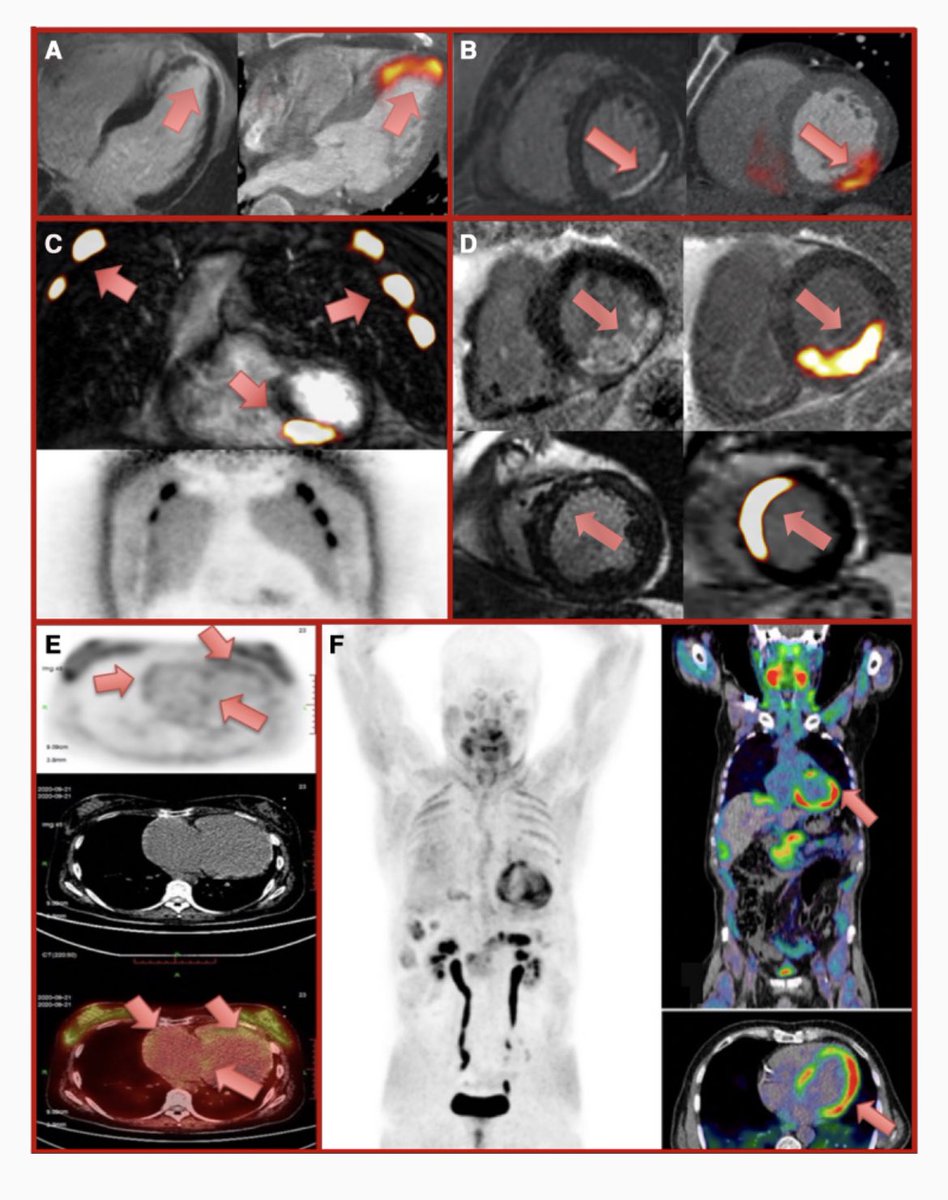

#Multimodalityimaging in 🫀 Sarcoidosis #Advances36 🔘LGE=inflammation OR scar and Rx is different for each state 🔘 FDG PET: assess/extra cardiac inflammation BUT intense dietary prep 🔘FDG=prognostic implications 🔘Novel SPECIFIC inflammation tracers are coming (DOTATATE/FLT)

🔘LGE=inflammation OR scar and Rx is different for each state

🔘 FDG PET: assess/extra cardiac inflammation BUT intense dietary prep

🔘FDG=prognostic implications

🔘Novel SPECIFIC inflammation tracers are coming (DOTATATE/FLT)